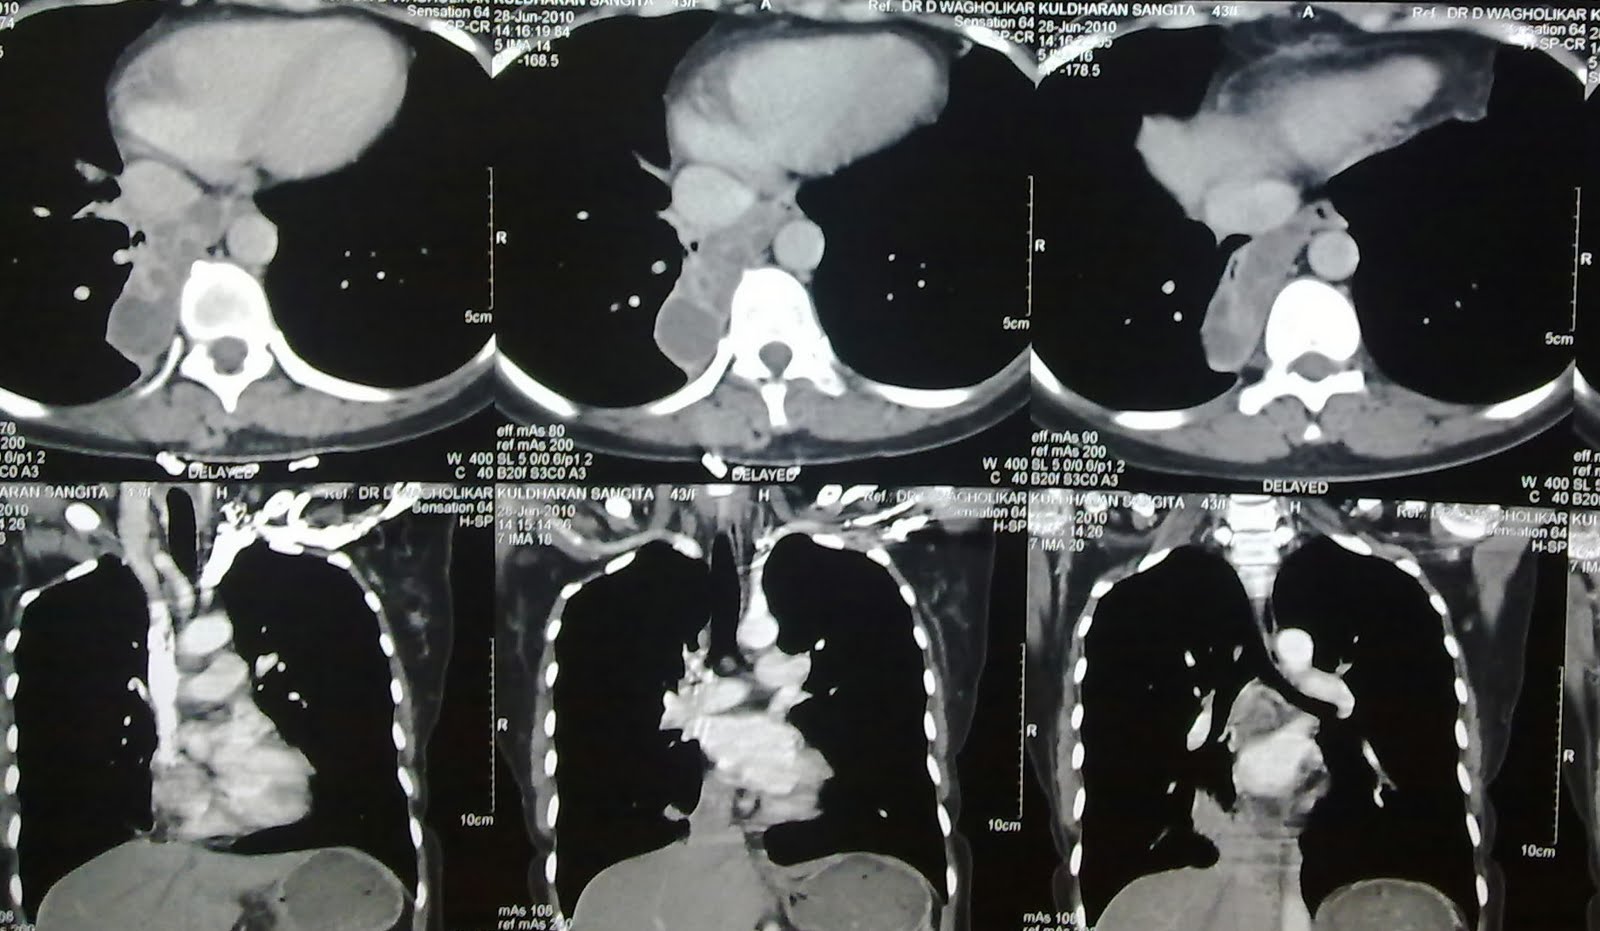

65 year old female,severe exertional dyspnoea,severe fixed obstruction and restriction on spirometry,progressive worsening in symptoms.write the radiological diagnosis.